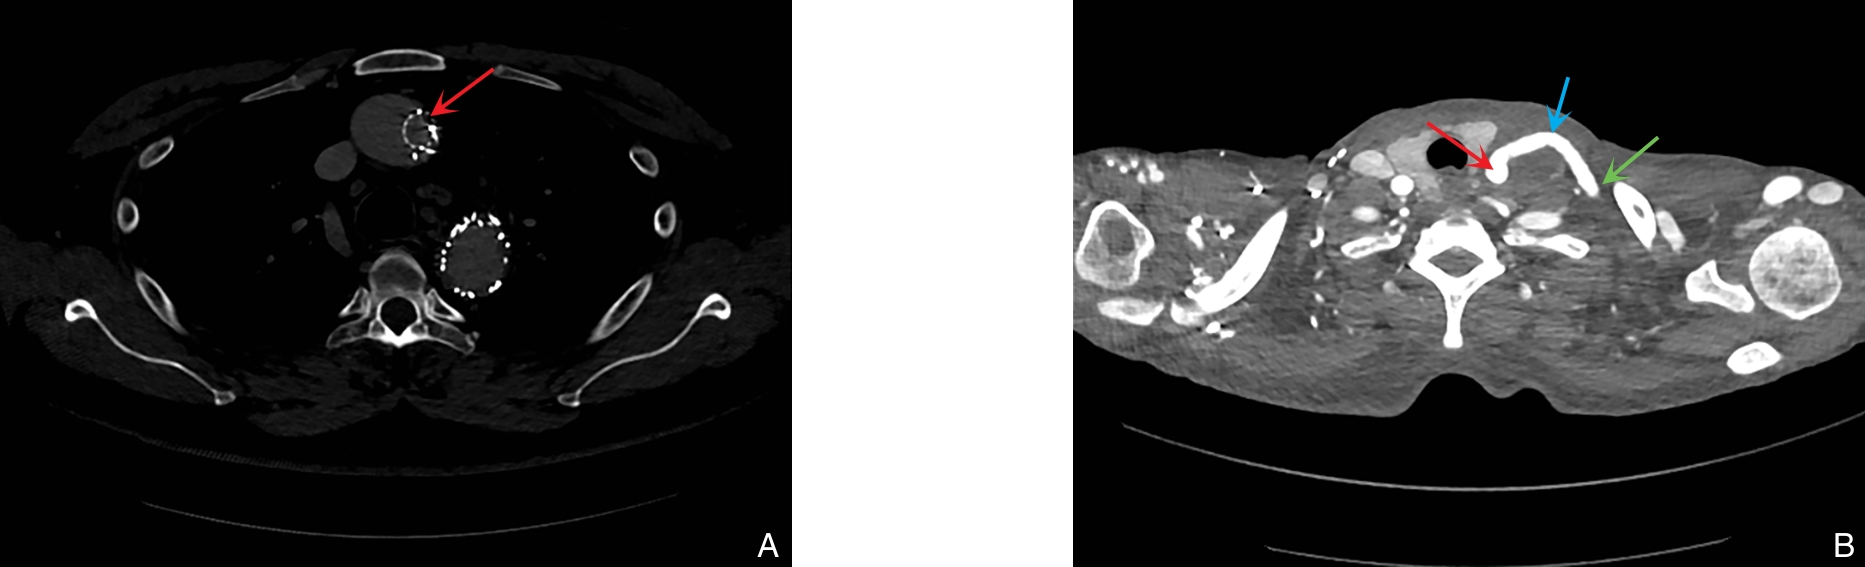

2025, 34(12):2664-2671. doi: 10.7659/j.issn.1005-6947.250617

摘要:背景与目的 中心静脉狭窄或闭塞(CVSO)影响血液透析疗效,但最佳静脉入路策略尚不明确。本研究比较单向静脉入路(UVA)与双向静脉入路(BVA)在维持性血液透析患者CVSO行经皮腔内血管成形术(PTA)或支架植入术(PTS)时的适用条件及技术成功率、临床成功率,并根据病变的位置和类型进行分层分析,旨在为不同病变制定个体化的静脉入路选择标准。方法 回顾性分析2019年7月—2024年2月赣南医科大学第一附属医院及南昌大学第二附属医院63例维持性血液透析CVSO患者的临床资料,其中UVA组37例、BVA组26例。比较不同静脉入路在CVSO介入治疗中的技术成功率(残余狭窄<30%)、临床成功率(症状缓解)及通畅率。结果 两组患者基线特征差异无统计学意义(均P>0.05)。总体技术成功率与临床成功率在UVA组与BVA组之间差异均无统计学意义(均P>0.05)。亚组分析显示,UVA组在上腔静脉及头臂静脉狭窄中的技术成功率高于BVA组,且UVA组在头臂静脉狭窄中的临床成功率高于BVA组;而在锁骨下静脉闭塞中,BVA的技术成功率及临床成功率均优于UVA(均P<0.05)。两组6个月及12个月一期、二期通畅率差异均无统计学意义(均P>0.05)。结论 对于上腔静脉或头臂静脉狭窄,优先采用UVA可获得较高的成功率;而在锁骨下静脉闭塞的介入治疗中,BVA更具优势。基于病变部位和类型合理选择静脉入路,有助于提高CVSO介入治疗的成功率并降低操作难度。